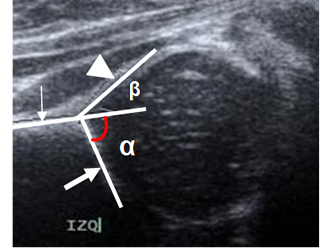

En la cadera se utiliza la ecografía para determinar la presencia de derrame articular y el estudio de la displasia en los recién nacidos.

Se traza el ángulo alfa en una vista coronal, sobre la parte media del acetábulo. Se mide entre la línea de base (Prolongación del iliaco) y la línea del techo óseo (Del borde inferior del iliaco, hasta el extremo óseo del acetábulo). Representa la excavación ósea del acetábulo y su amplitud normal debe ser igual o mayor de 60º y disminuye en casos de displasia. (2, 6). (Fig 19).

Fig 19. Angulos de la cadera.

Ecografía. Línea de base (Flecha delgada), línea del techo óseo (Flecha gruesa) y línea del techo cartilaginoso (Punta de flecha). Angulo alfa normal, con amplitud mayor de 60.